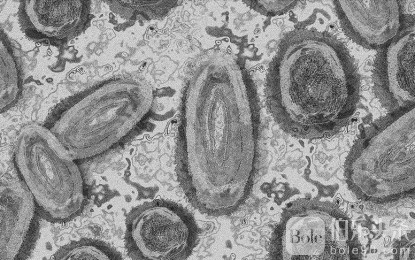

瑞典确认非洲以外首例mpox变种病例

伯乐头条专讯:据当地媒体报道,瑞典周四报告了非洲以外首例传染性更强的 mpox 变种病例。

目前在刚果民主共和国和非洲大陆其他地区传播的 mpox 变种被认为比导致 2022 年开始的全球疫情的“进化枝 2”变种更具传染性和致命性。